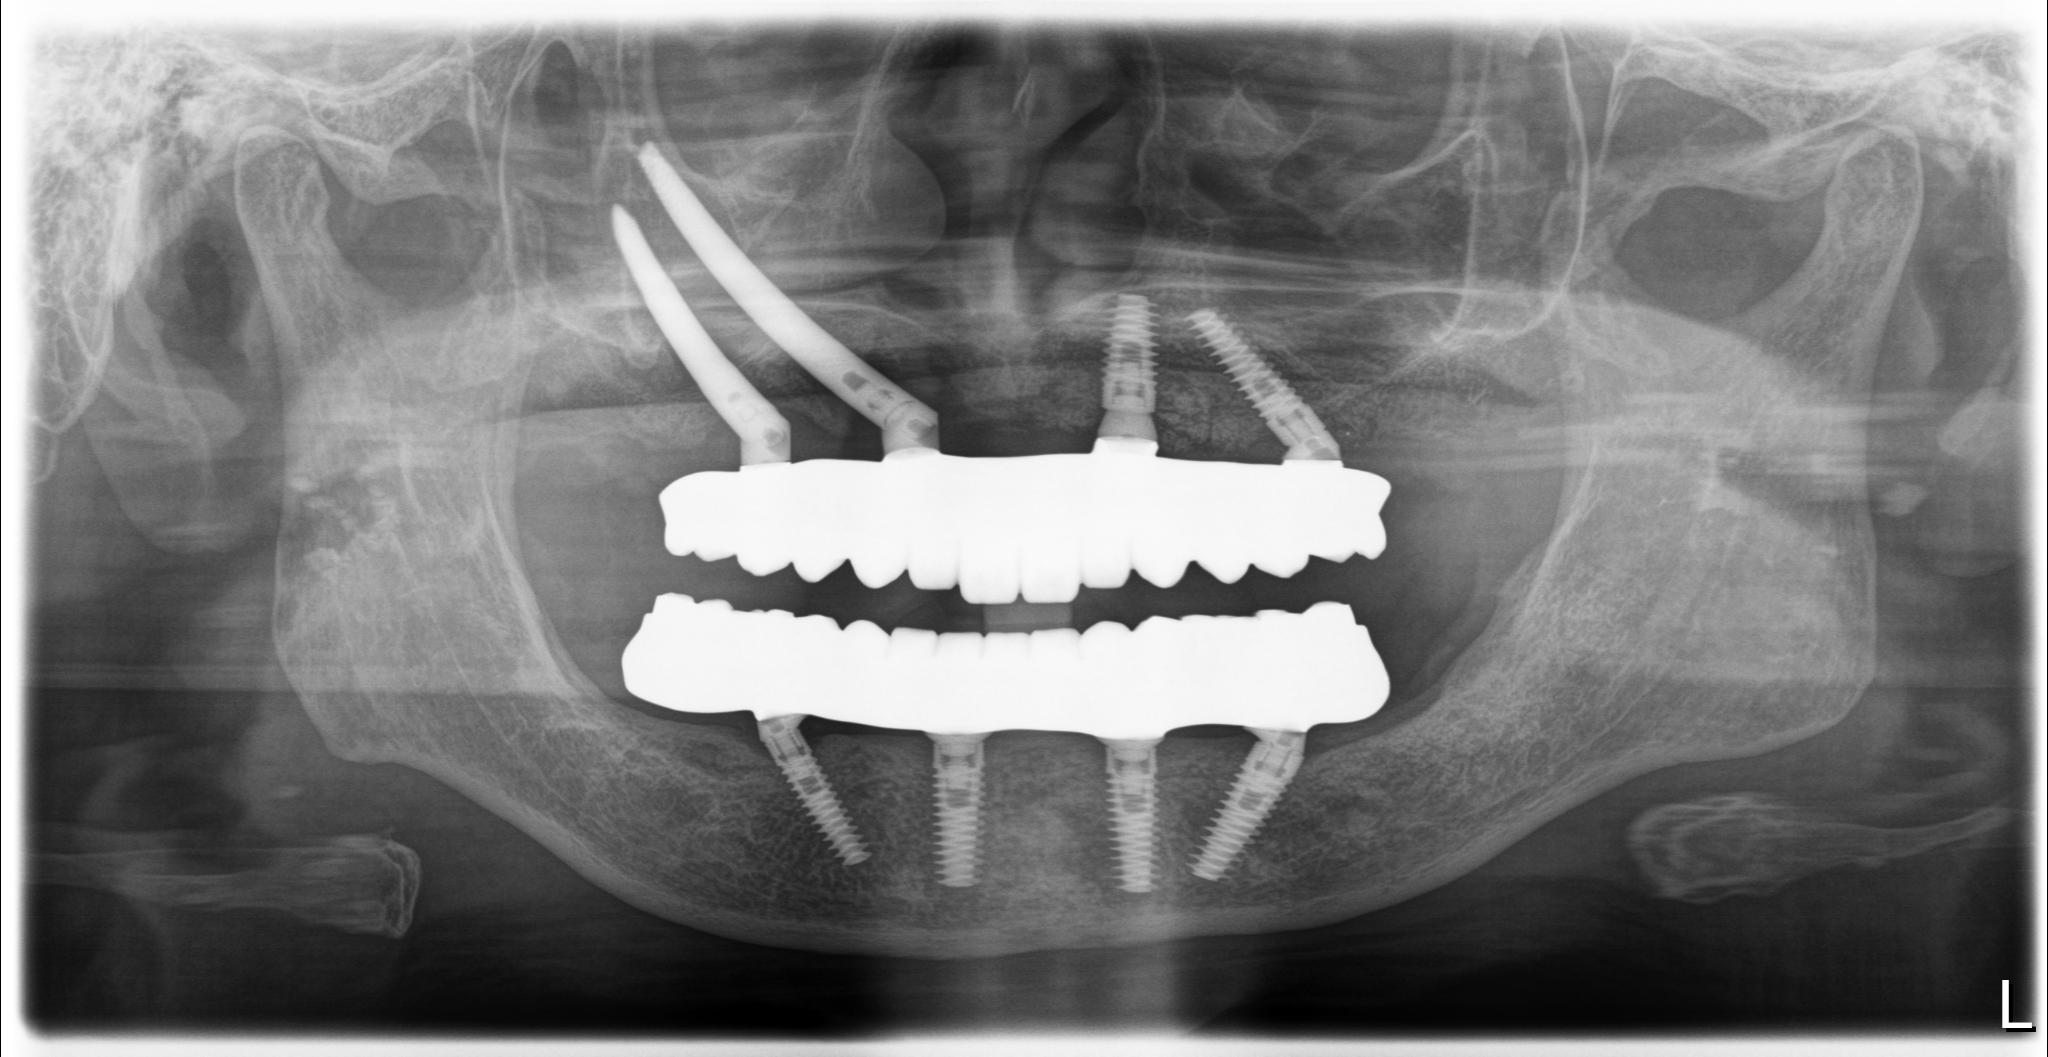

内容 :上下顎オールオン4ザイゴマ2

費用 :5,552,800円

※モニター価格

期間 :半年

リスク:出血・腫れ・痺れ・痛み